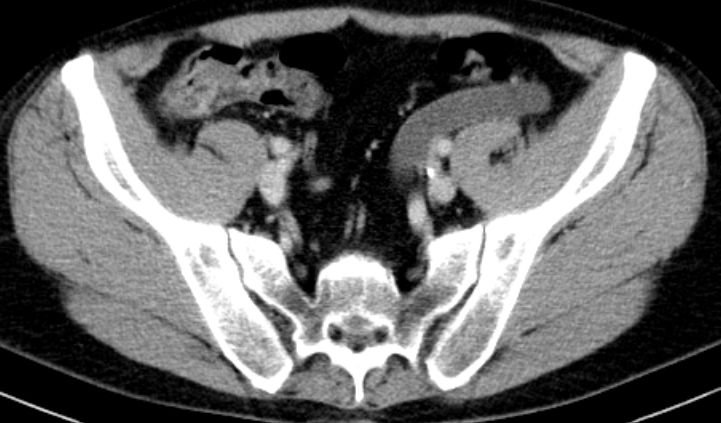

Entdifferenziertes Urothelkarzinom des rechten proximalen Harnleiters pT4 G3 L1